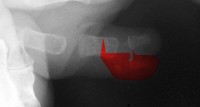

| Case 1. Wassell IV duplication of the proximal and distal phalanges, with characteristic deviation of the thumbs away from each other at the MCP and toward each other at the IP joints. This was corrected by metacarpal head narrowing, opposing closing wedge osteotomies of the metacarpal and proximal phalanx and collateral ligament reconstruction using parts from the deleted digit. |